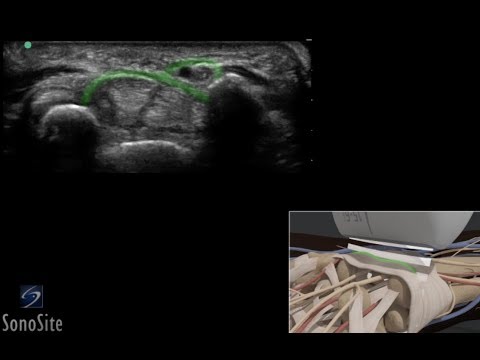

Elbow Ultrasound Normal Vs Abnormal Images | Muscles Tendons Ligaments and Nerves MSK USG

Flexor Tenosynovitis Caused by Retained Foreign Body